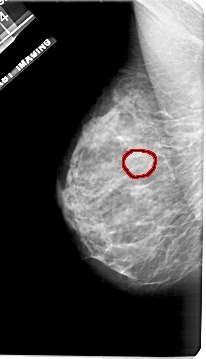

A_1921_1.LEFT_CC

LEFT_CC LINES 5011 PIXELS_PER_LINE 2851 BITS_PER_PIXEL 12 RESOLUTION 43.5 OVERLAY

FILE: A_1921_1.LEFT_CC.OVERLAY

TOTAL_ABNORMALITIES 1

ABNORMALITY 1

LESION_TYPE MASS SHAPE OVAL MARGINS OBSCURED

ASSESSMENT 3

SUBTLETY 2

PATHOLOGY BENIGN

TOTAL_OUTLINES 1

BOUNDARY